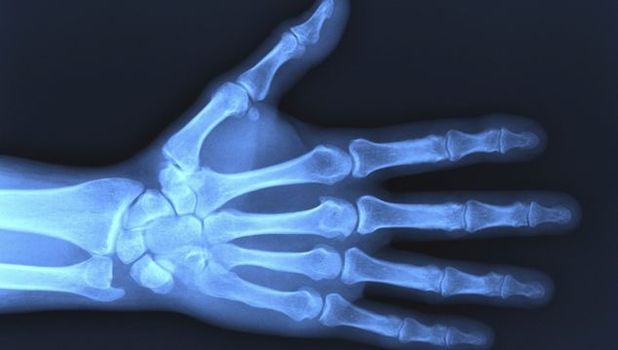

After the truly shocking X-ray of a man with a 10cm fork stuck inside his penis, we had to go looking for more weird stuff that the X-ray machines have captured.